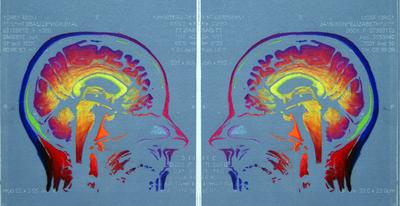

Emerging, Solarplate etching based on the MRI of the artist

Utilizing state-of-the-art neuroimaging technologies, my artwork displays parts of the brain in ways that are rarely seen outside of the medical and scientific community.

My etchings and digital collages express the beauty and mystery of the brain revealed through my own MRI images of my brain. Brain scans became a major part of my life when I was diagnosed with Multiple Sclerosis in 1992.

As the stack of MRIs grew in my studio, so did my fascination with the brain and the eerie black and white images that seemed to hold my fate. The digital images of my brain were frightening, yet also immediately mesmerizing.

The art that resulted came from an urge to reinterpret these images, to use them to explore the wonder and the complexity of all brains-including those with the disease.

My intent is to create images that show the splendor of the brain, with all its powers to change, adapt, and confound. This work expands the conventional definition of portraiture by questioning what it means to be human, and by challenging viewers to see themselves as more than simply their likeness.